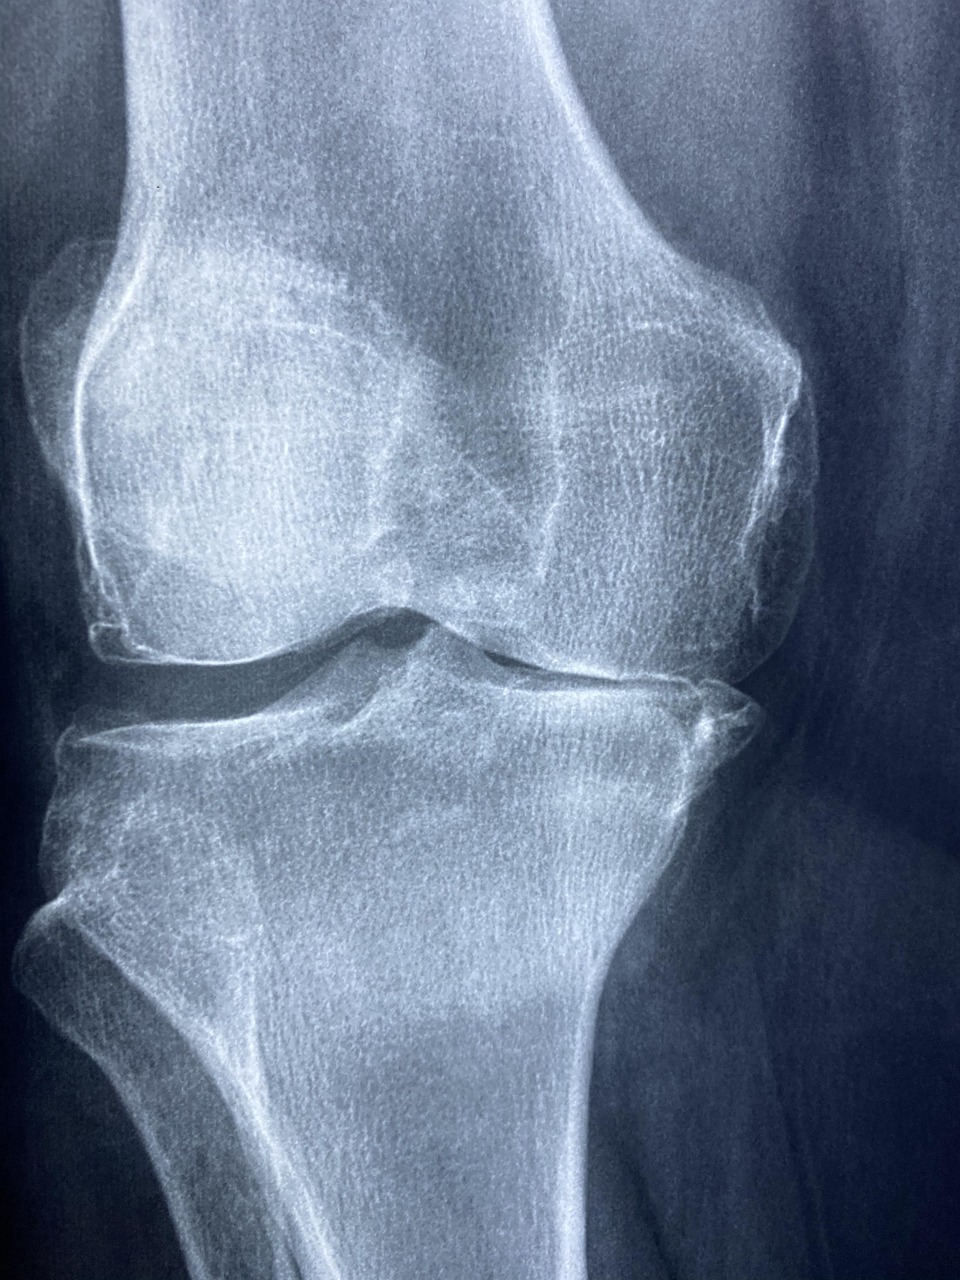

최근 들어 특별한 외상이 없는데도 고관절이나 무릎 부위에 통증이 반복되고, 병원에서는 단순한 관절통으로 진단받았다면 ‘무혈성 골괴사’를 한 번쯤 의심해 볼 필요가 있습니다. 초기에는 X-ray로도 발견되지 않을 만큼 증상이 모호하지만, 병이 진행되면 일상적인 보행조차 어려울 만큼 심각한 상태로 발전할 수 있기 때문입니다. 특히 30~50대 중장년층이나 스테로이드를 장기간 복용한 이력, 과도한 음주 습관이 있는 사람에게서 무혈성 골괴사(AVN, Avascular Necrosis) 발생률이 높다는 점은 간과할 수 없습니다.

무혈성 골괴사는 방치하면 뼈가 점차 무너지고 관절면이 불규칙하게 변형되며, 이로 인해 관절염이 발생하거나 연골이 손상되는 이차적인 문제로 이어질 수 있습니다. 이 단계에 이르면 더 이상 약물치료나 보존적 치료로는 회복이 어려워지고, 결국 인공관절 수술을 고려해야 하는 상황에 이를 수 있습니다. 따라서 이러한 진행을 막기 위해서는 조기 진단이 가장 중요하며, MRI 검사는 초기 진단에 매우 유용한 도구로 활용됩니다.